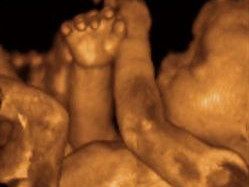

3D/4D ultrazvuk poskytuje unikátní možnost sledovat detailní trojrozměrné obrazy (3D) a dokonce i reálný pohyb jejich nenarozeného dítěte (4D). Díky této technologii mohou rodiče prozkoumat tvářičku, končetiny a orgány dítěte s neuvěřitelnou jasností a živostí.

„Náš tým kvalifikovaných lékařů je zde, aby poskytl podporu a vysvětlili všechny získané informace, což zajišťuje klid a jistotu budoucím rodičům. Využití této pokročilé technologie může napomoci také časné detekci případných abnormalit a umožňuje včas přijmout potřebná opatření," doplňuje primář.